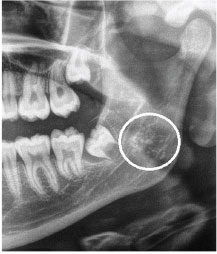

9. What condition can be seen in the following X ray? (the circle)